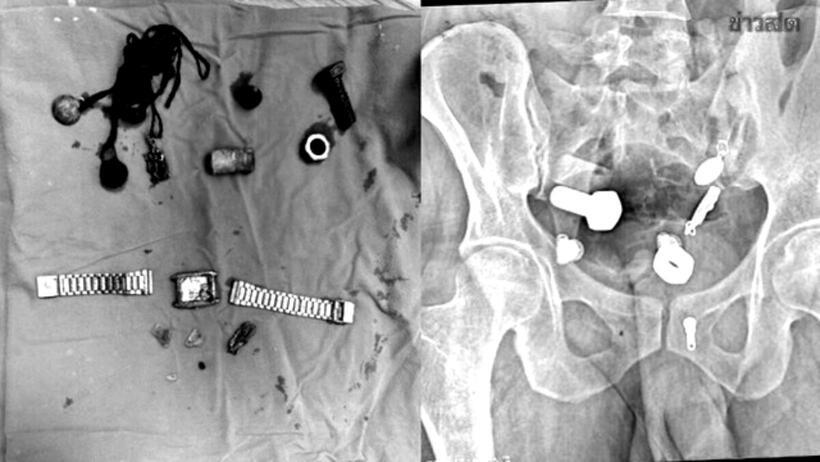

Sau khi thăm khám và chụp X-quang, các bác sĩ thấy một chiếc đồng hồ đeo tay, bu lông và ốc vít, được gắn chặt vào nhau... trong bụng bệnh nhân.

Dị vật được lấy ra từ bụng người đàn ông.

Các bác sĩ đã cố gắng sử dụng ống nội soi để lấy vật thể ra nhưng không thành công, sau đó phải tiến hành một cuộc phẫu thuật lớn kéo dài hơn ba giờ để lấy toàn bộ dị vật ra khỏi cơ thể.

Theo Khaosod, đội ngũ y tế "sốc ngang" khi thấy nhiều vật thể, bao gồm cả một chiếc đồng hồ đeo tay trong bụng nam bệnh nhân. Sau phẫu thuật vài ngày tình hình sức khỏe bệnh nhân đang hồi phục tốt.